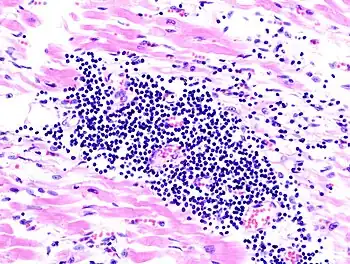

Many pathologists seek fellowship-level training, or otherwise pursue expertise in a focused area of surgical pathology. Subspecialization is particularly prevalent in the academic setting, where pathologists may specialise in an area of diagnostic surgical pathology that is relevant to their research, but is becoming increasingly prevalent in private practice as well. Subspecialization has a number of benefits, such as allowing for increased experience and skill at interpreting challenging cases, as well as development of a closer working relationship between the pathologist and clinicians within a subspecialty area. Commonly recognized subspecialties of surgical pathology include the following:

- Hematopathology (A board-certifiable subspecialty in the U.S.)